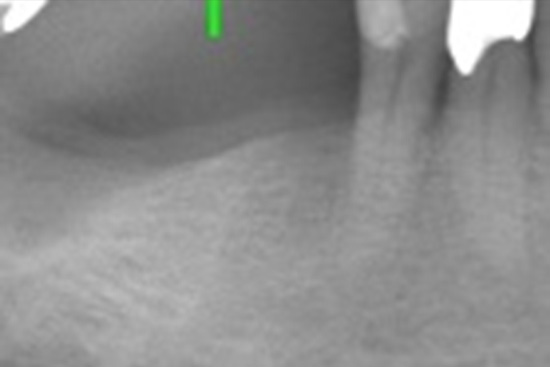

インプラント治療の症例

治療前

治療後

| 主訴 | 歯がない所が気になる |

|---|---|

| 治療期間 | 3ヶ月 |

| 治療内容 | インプラント |